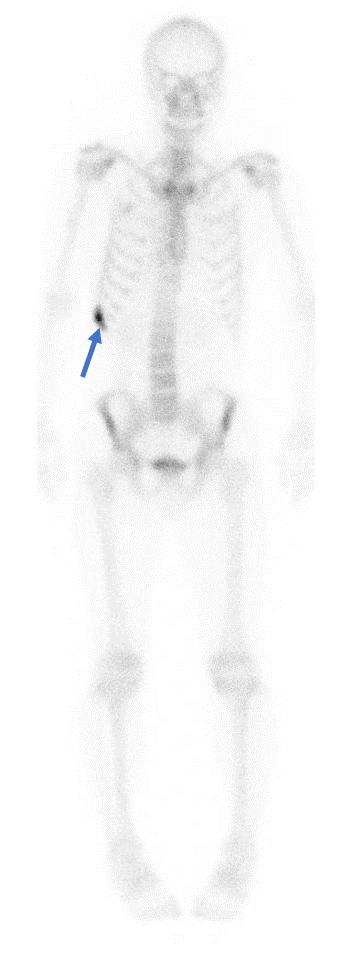

人体骨骼放射扫描图像

在线等——做全身骨扫描说是右侧肱骨上段左侧股骨头局限性骨代谢增高

求影像核医学专业的医生帮看一下我母亲的spect(全身骨扫描)结果,图片

骨扫描图片

正常骨扫描图片

全身骨扫描图片

骨扫描显示骨转移图片

肺癌骨转移骨扫描图片